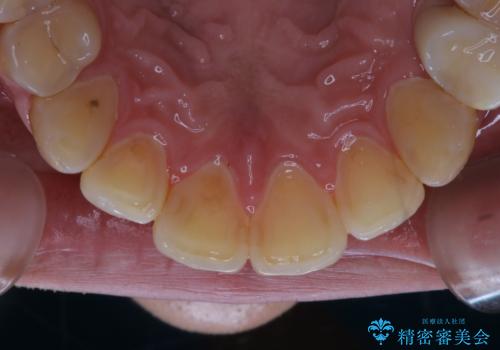

紅茶による着色を1日できれいに

- 紅茶を頻繁に飲むため、歯の黄ばみが気になるとのことでした。PMTC60分コースを行いました。

PMTC(保険外治療)は、毎日の歯磨きで落としきれない汚れや、コーヒ、紅茶・タバコのヤニなどの着色も除去します。目には見えない歯と歯の間・歯肉の境目などに残っているプラーク(歯垢)もしっかり取り除きます。PMTCでは専門的な機械や材料を使用して、徹底的に汚れを除去するため、虫歯・歯周病・口臭予防などにつながります。